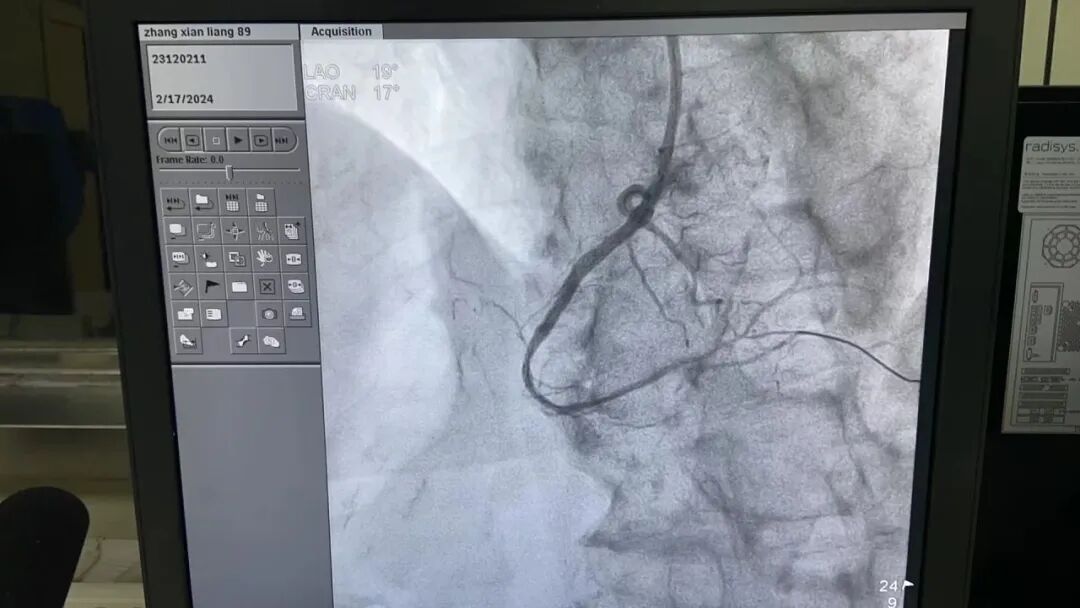

90岁的张爷爷三年前出现反复胸痛、胸闷等不适,虽经多家医院治疗,但病情一直反反复复,最近更是胸闷难忍,在家人的陪同下来我院就诊。心内二科邱治芬主任接诊后,详细询问病史并完善相关检查,建议患者行冠状动脉造影检查以明确诊断。冠状动脉造影提示三支主要血管严重病变,其中右侧冠脉血管完全堵塞,左侧血管最重狭窄达到90%,严重威胁生命。

术前

术后